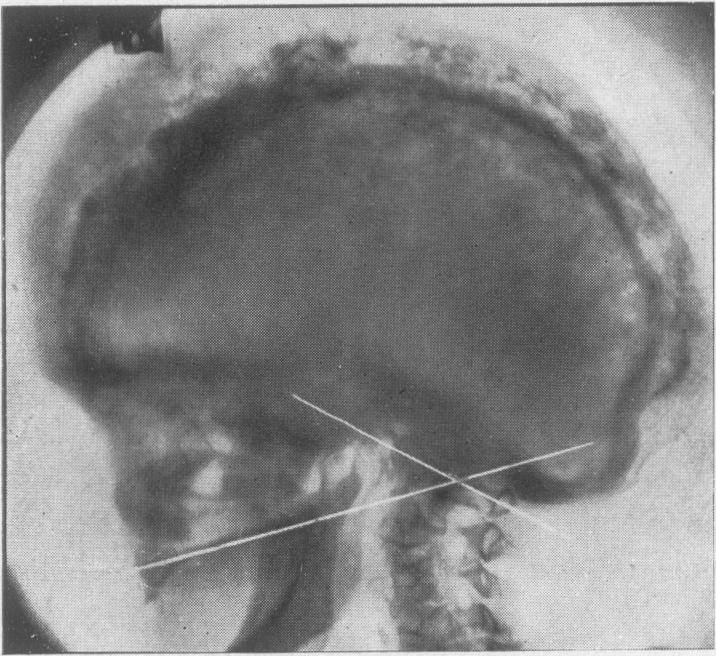

Bull J

Proc R Soc Med. 1946 Dec;40(2):85-7. doi: 10.1177/003591574604000215.